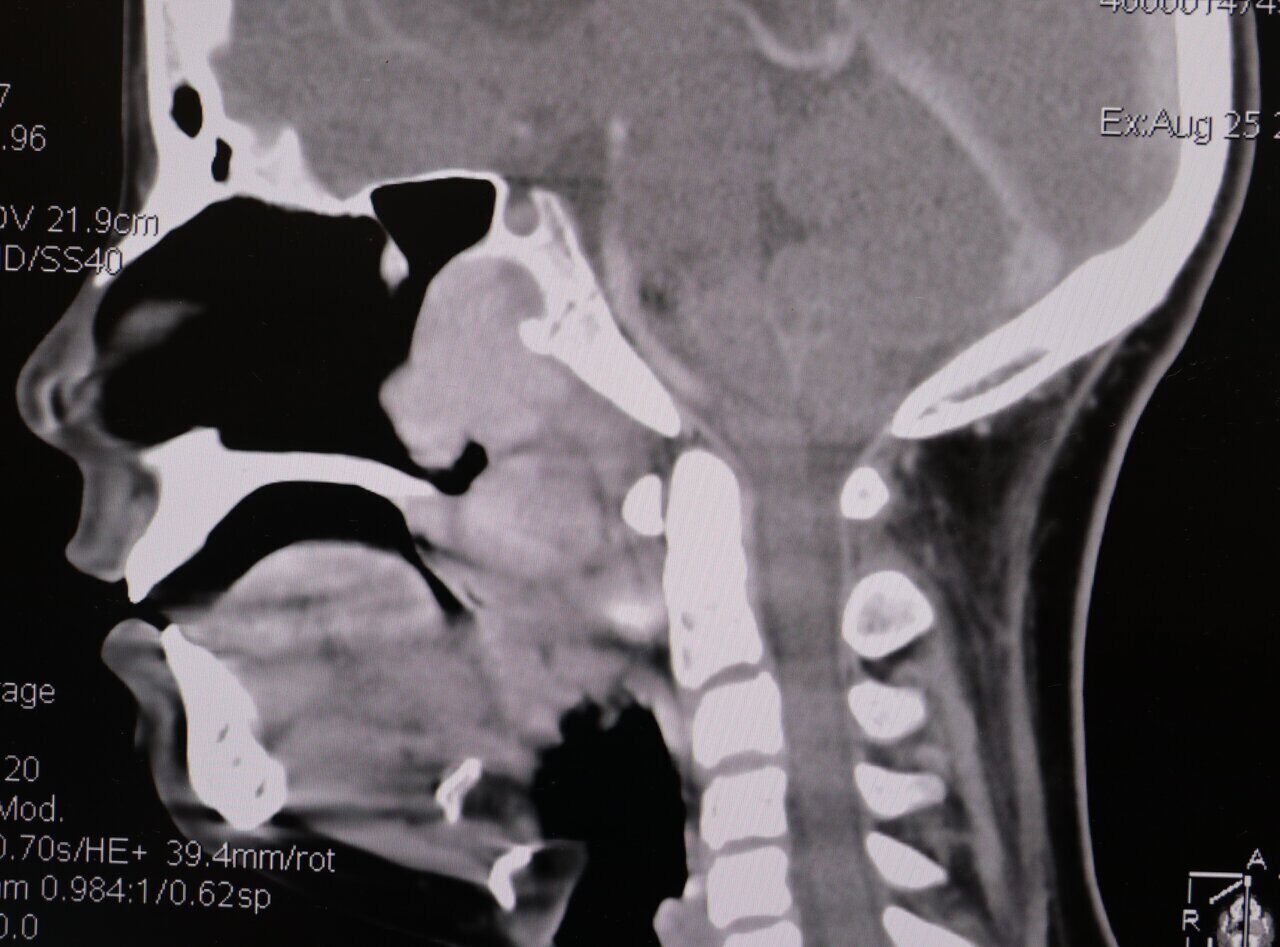

Все о назофарингеальной карциноме: симптомы и лечение